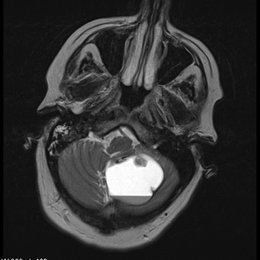

PREGUNTA 4 de 10

¿Cuál es el diagnóstico más probable de la siguiente imagen?

A)

quiste aracnoideo

B)

Quiste de la bolsa de Rathke

C)

craneofaringioma

D)

Silla turca vacía

E)

macroadenoma hipofisario